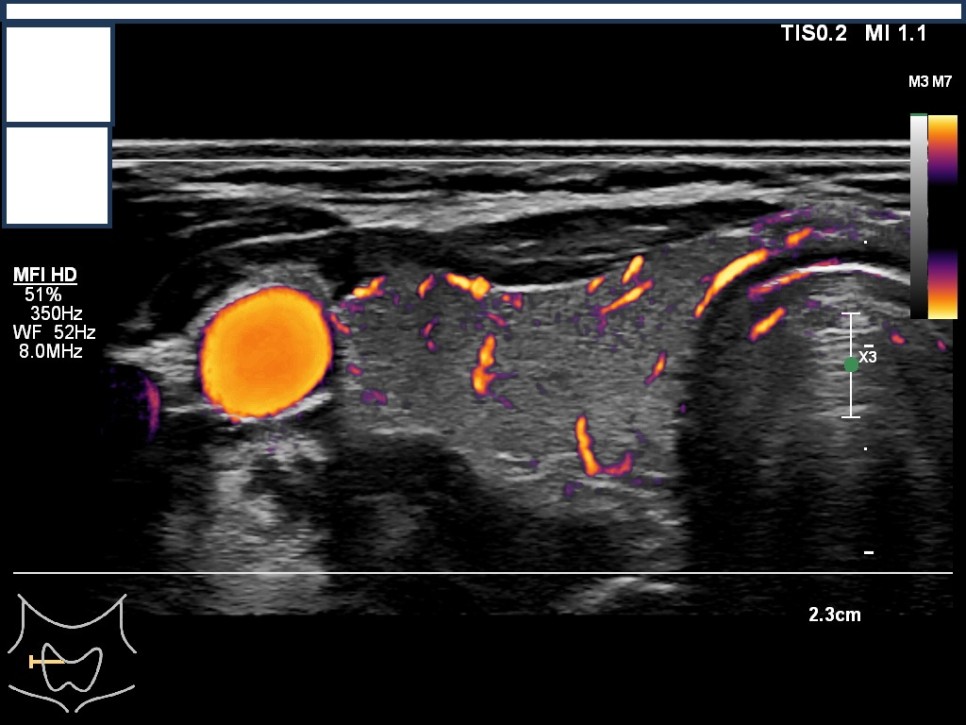

갑상선, 부갑상선 초음파 검사 급여 기준 1. 표준 영상의 범위 모든 영상에는 경부의 해부학적 위치(모식도나 문자)를 표기하여야 한다.

A) 병변이 없는 경우: 우엽 중부 가로 스캔, 우엽 중앙부 세로 스캔, 협부 가로 스캔, 좌엽 중부 가로 스캔, 좌엽 중앙부 세로 스캔, 우경부 림프절, 좌경부 림프절 나) 병변이 있는 경우: 병변이 없는 경우의 표준 영상과 함께 병변 부위에서 2개의 수직 관계 단면 영상(횡단/종단) 및 병변의 크기가 측정된 경우: 병변이 없는 경우의 표준 영상

Color Doppler / 우측 경부 림프절 Level1-4 / 우측 경부 림프절 level5